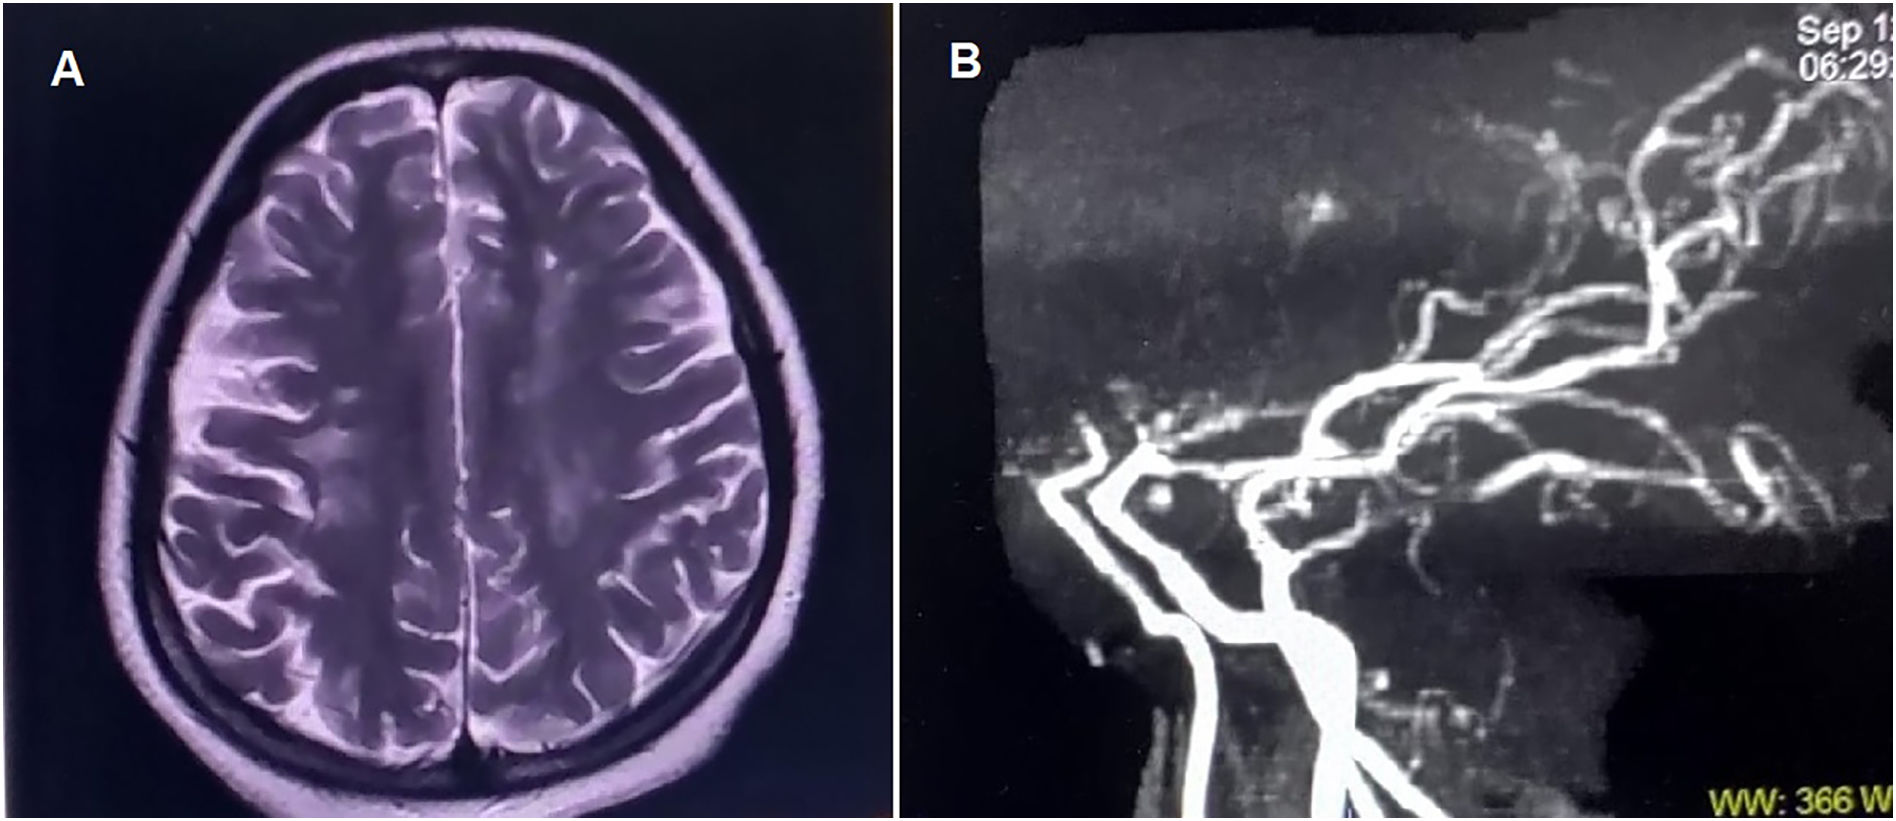

Neurodegeneration with brain iron accumulation: two decades of pediatric cases in a Portuguese Center

Background Neurodegeneration with brain iron accumulation (NBIA) comprises a group of rare and heterogeneous genetic disorders, in which early diagnosis can be challenging. Cases Retrospective review of clinical, neurophysiological, radiological, and molecular data from 18 […]